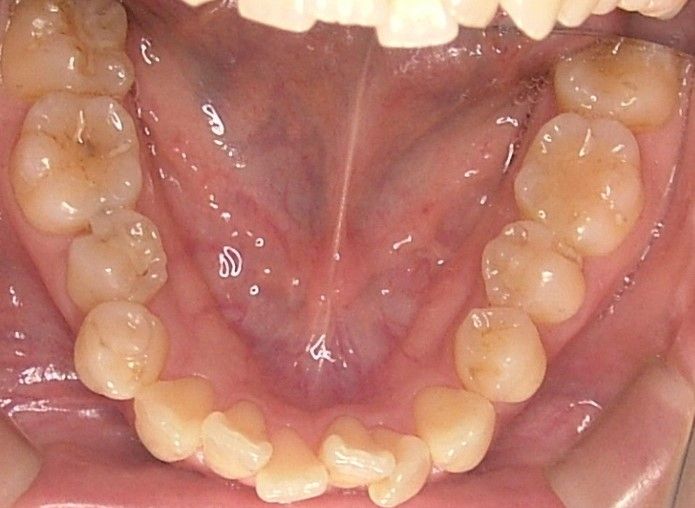

初診時 |

口腔内写真 |

| 治療内容 | 掌蹠膿疱症、不定愁訴も治したい。花粉症もあり。ガルバニー電流測定、オリゴスキャン検査、ビタミンDの血中濃度測定 |

|---|---|

| 治療期間・回数 | 5か月・30回 |

| 治療時の費用 | 1,200,000円(メタルフリー代、サプリメント代) ※本症例当時の価格です。最新の費用はこちら |

| リスク・副作用 | 金属除去後に熱が出たそうですが、一時的な好転反応と思われます。このような症状は個人差があるので、特に心配はありません。 |